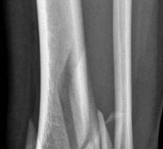

Tibial shaft fracture extending into the plafond—intramedullary fixation Case description a A 25-year-old wom…

Tibial shaft fracture extending into the plafond—plate fixation Case description A 26-year-old man fell from …